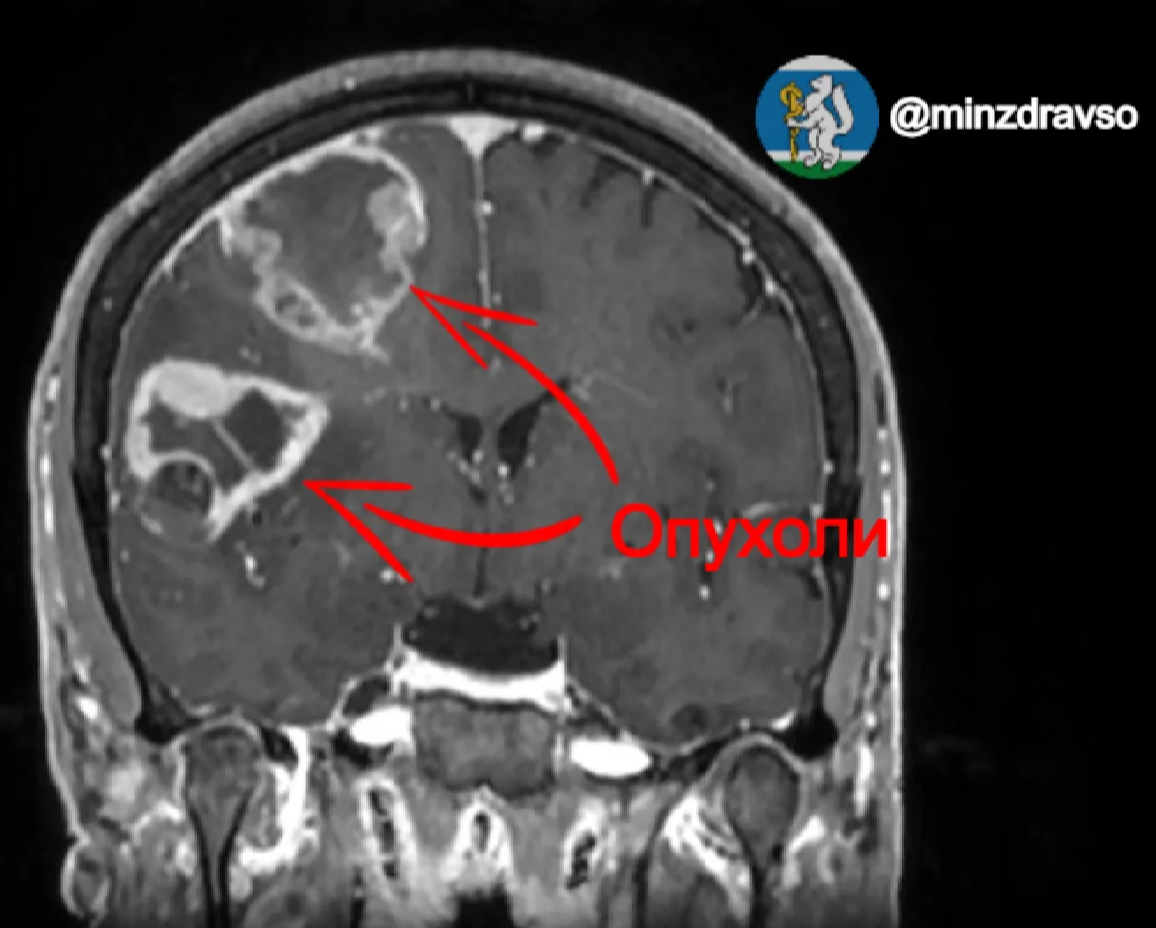

Нейрохирурги Свердловского областного онкологического диспансера за одно хирургическое вмешательство успешно удалили сразу две злокачественные опухоли правого полушария головного мозга у 50-летней пациентки. Случай примечателен тем, что парные глиомы — редкое явление, как правило, они вызывают серьёзные неврологические нарушения. Но в данном случае новообразования удалось обнаружить в нескольких миллиметрах от важных двигательных центров, что позволило сохранить функции организма свердловчанки после хирургического вмешательства.

Заболевание заявило о себе в декабре прошлого года: тогда у 50-летней свердловчанки впервые случился эпилептический припадок. В ходе углублённой диагностики было выявлено три очага опухоли: два из них размером примерно 3х4 сантиметра находились в правой лобной доле, которая отвечает за движение. Третье новообразование размером около 7 миллиметров располагалось в левой доле, ответственной за речь, память и другие когнитивные навыки.

Нейрохирург Свердловского областного онкологического диспансера Павел Гвоздев отметил, что впервые за 27 лет практики столкнулся с глиомами, расположенными настолько «удачно»: несмотря на достаточно большой объём, они ещё не успели прорасти в важные центры головного мозга, хоть и находились совсем рядом. Этот фактор в совокупности с опытом и мастерством хирургической бригады позволил радикально удалить сразу два новообразования.